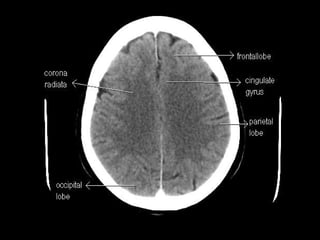

Radiographers use medical imaging equipment like X-rays and MRIs to produce images of patients' internal structures and organs. They are responsible for positioning patients, operating scanning machines, and ensuring quality images. Radiographers must have strong attention to detail, excellent communication skills, and the ability to work well under pressure to accurately capture anatomical features and diagnose any abnormalities.